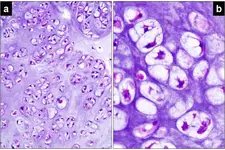

Tanı Yöntemleri Burun kıkırdak eğriliğinin tanısı, genellikle bir kulak burun boğaz uzmanı tarafından yapılır. Tanı sürecinde kullanılan yöntemler şunlardır: